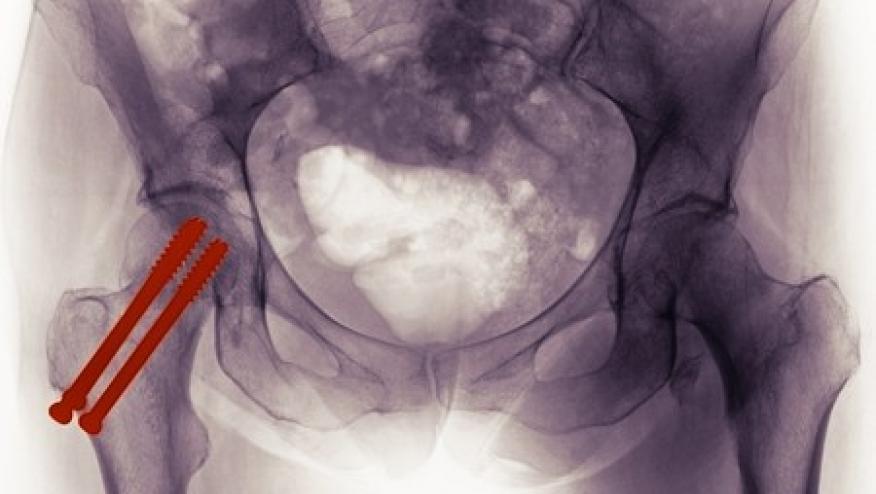

A new nationwide Austrian cohort study was designed to assess effect of PPI use on mortality rate after osteoporosis related hip fracture. (Citation source: http://buff.ly/2jRAhYK)

The study evaluated 31,668 Austrian patients >50 years with a history of hip fracture between July 2008 and December 2010. Patents with a history of PPI use before or after fracture related hospitalization, their mortality cause and bone strengthening medication were compared to patients with no history of PPI or anti-osteoporosis medication use in Cox regression analysis.